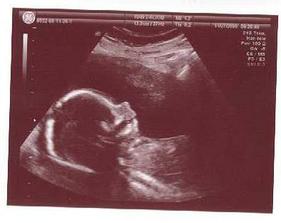

19.9. ..mrňousek mi zamaval a pan doktor udelal krasnou fotecku ..dalsi kontrola